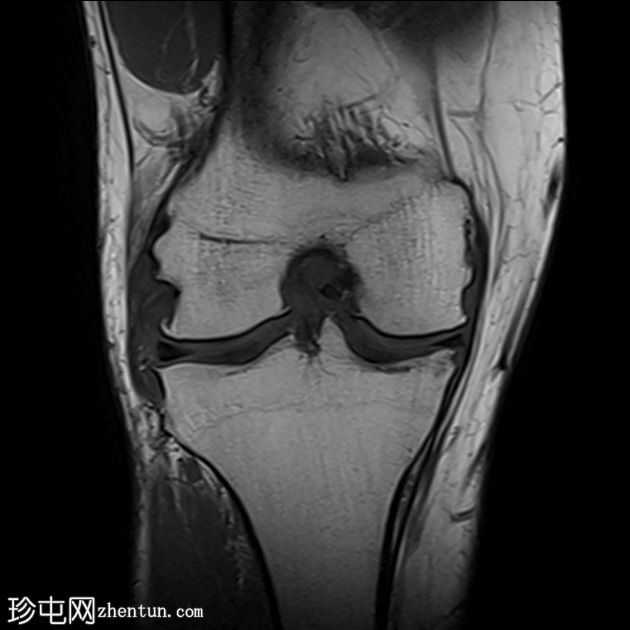

膝关节周围痛风

右膝关节疼痛、肿胀、活动受限,并有长期痛风病史。

年龄:45岁

性别:男

MRI

T2和PD脂肪饱和序列上可见多处轻微高信号区,位于股四头肌腱远端、前交叉韧带、内侧副韧带近端1/3内表面深层、腘肌腱附着处。

少量膝关节积液。

其他发现包括:前交叉韧带腱鞘囊肿、膝关节后外侧轻度肌间液信号和轻度软骨软化。

印象:这些发现提示痛风性关节炎伴单钠尿酸盐晶体沉积。